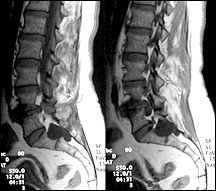

These cysts can occur anywhere in the spine, but the most common areas affected are the S-2 and S-3 nerve roots. Sacral cysts have been reported to cause sacral radiculopathy, hip, leg or foot pain, perineal pain, paresthesias, and bowel or bladder dysfunction. Symptoms can mimic a disc herniation.

There are many variations of Tarlov cysts. Some can become quite large - up to 6 cm. They can be multiple. As you might suspect, there is some confusion over the precise definition of Tarlov cysts and how they are different from other spinal cysts. The distinctive feature of the Tarlov perineurial cyst is the presence of spinal nerve root fibers within the cyst wall or cyst cavity itself.

Unfortunately, there is no consensus yet as to the best way to manage these lesions. With improved imaging, these cystic lesions are becoming more apparent and most of the time they are considered incidental findings; the problem occurs when differentiating these cysts from other causes for the patient's symptoms, such as degenerative disc and joint disease.